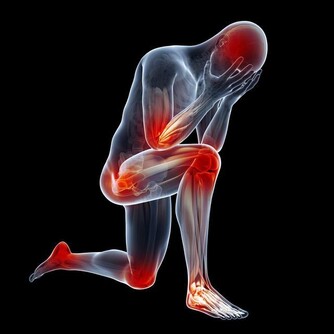

4、影響長高

吃糖過多,還可以影響鈣質代謝。

有些學者認為吃糖量如果達到總食量的16-18%,就可使體內鈣質代謝紊亂,妨礙體內的鈣化作用。

據日本一項調查表明,小兒骨折率有所增加,他們認為糖過多是造成骨折的重要原因。